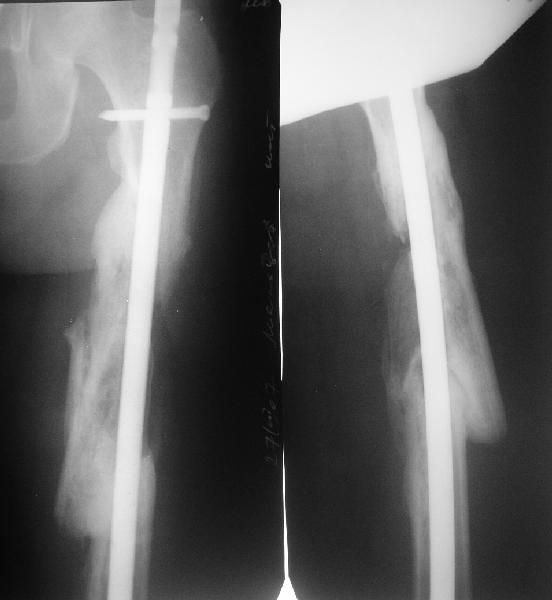

Мы бы не стали открывать, такие переломы срастаются, хотя бы и с

краевым дефектом. То есть если и удалять стержень потом, то сильно

попозже обычного. В приложении пример. Сразу после операции и через 11

мес. Понятное дело, пациент к тому времени давно и не хромал, и функция

колена была полная.